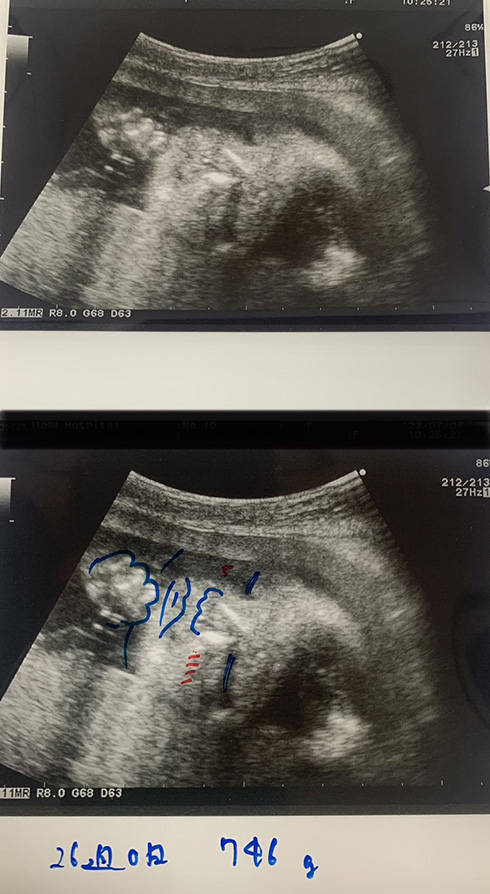

エコー写真のひと工夫とは、婦人科医の今井賢(@kunkun421)さんが行っている、“胎児の輪郭線を描き足す”というもの。元のモノクロ写真だと素人目には赤ちゃんの姿が把握しづらいですが、線を足すことで視認性が飛躍的に上昇。

赤ちゃんの体の輪郭や、目・鼻・口といった顔を大まかにガイドしてくれるので、赤ちゃんの生き生きとした様子が伝わってきます。

今井さんが「僕は必ず同じ写真を2枚にして片方に絵を描いて渡しています」と、この取り組みを紹介したところ、X(旧Twitter)上では「助産師外来でもぜひにやってみたい」といった医療関係者からの声や、「赤ちゃんへの愛情を感じちゃいます」といった感想が寄せられました。心遣いが感じられるすてきな工夫です。

画像提供:今井賢 Ken Imai@zoom婦人科医(@kunkun421)さん